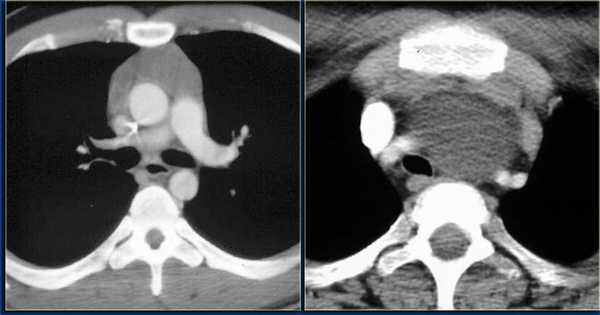

При проведении компьютерной томографии оценивают наличие вилочковой железы и положение в средостении: уровень и отношение к срединной линии, ее форму, линейные размеры, однородность структуры, четкость контуров, измеряют плотность нативно, а также в артериальную, венозную и отсроченную стадии. Аксиальные изображения КТ и комбинированные мультиплоскостные реконструкции могут быть использованы, чтобы идентифицировать инвазию опухоли в крупные кровеносные сосуды, перикард и легочную ткань. Если, опухоль имеет гладкие, четкие границы, однородную плотность, отсутствуют некрозы или кистозные изменения, видна жировая прослойка между опухолью и смежными структурами новообразование можно считать неинвазивным. Если, опухолевое новообразование имеет дольчатую или неправильную форму, нечеткие контуры, неоднородное усиление после внутривенного контрастирования, явное прорастание перикарда, легочной ткани, грудной стенки такую опухоль необходимо считать инвазивной.

Дифференциальная диагностика между гиперплазией и тимомой (рис.3-7) небольших размеров заключается в выявлении новообразования, локально выходящего за контур железы накапливающего контрастное вещество в разные фазы контрастирования отлично от неопухолевой ткани вилочковой железы.